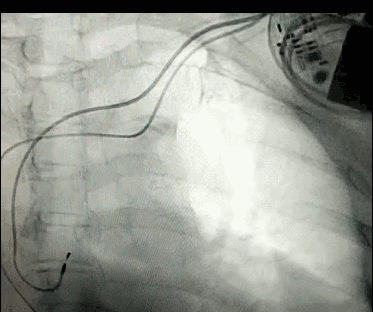

DSA是將造影劑注入需要檢查的血管中,使血管顯露原形,然后通過(guò)系統(tǒng)處理,使血管顯示更加清晰,便于醫(yī)生診斷或進(jìn)行手術(shù)。

數(shù)字減影血管造影術(shù)是醫(yī)學(xué)影象學(xué)中,繼X線CT之后的又一項(xiàng)新技術(shù),也是當(dāng)前醫(yī)學(xué)影象學(xué)中具有突破性的重大進(jìn)展。?